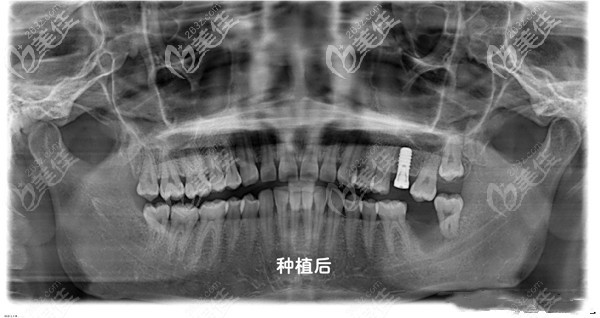

醫(yī)生介紹:杭州北樂口腔的江醫(yī)生畢業(yè)于河北省華醫(yī)口腔,是北樂口腔機構的院長,他擅長成人矯正、兒童矯正、牙齒種植、牙齒美容修復及各種復雜修復,牙周治療。同時,他是美國invisalign隱適美隱形矯正醫(yī)師,登騰種植系統(tǒng)專業(yè)醫(yī)師,其擅長將各類常用的先進矯治技術與國人的口腔特點巧妙結合,給顧客呈現(xiàn)好的技術。另外,江曉亮醫(yī)生精通隱形矯正、...